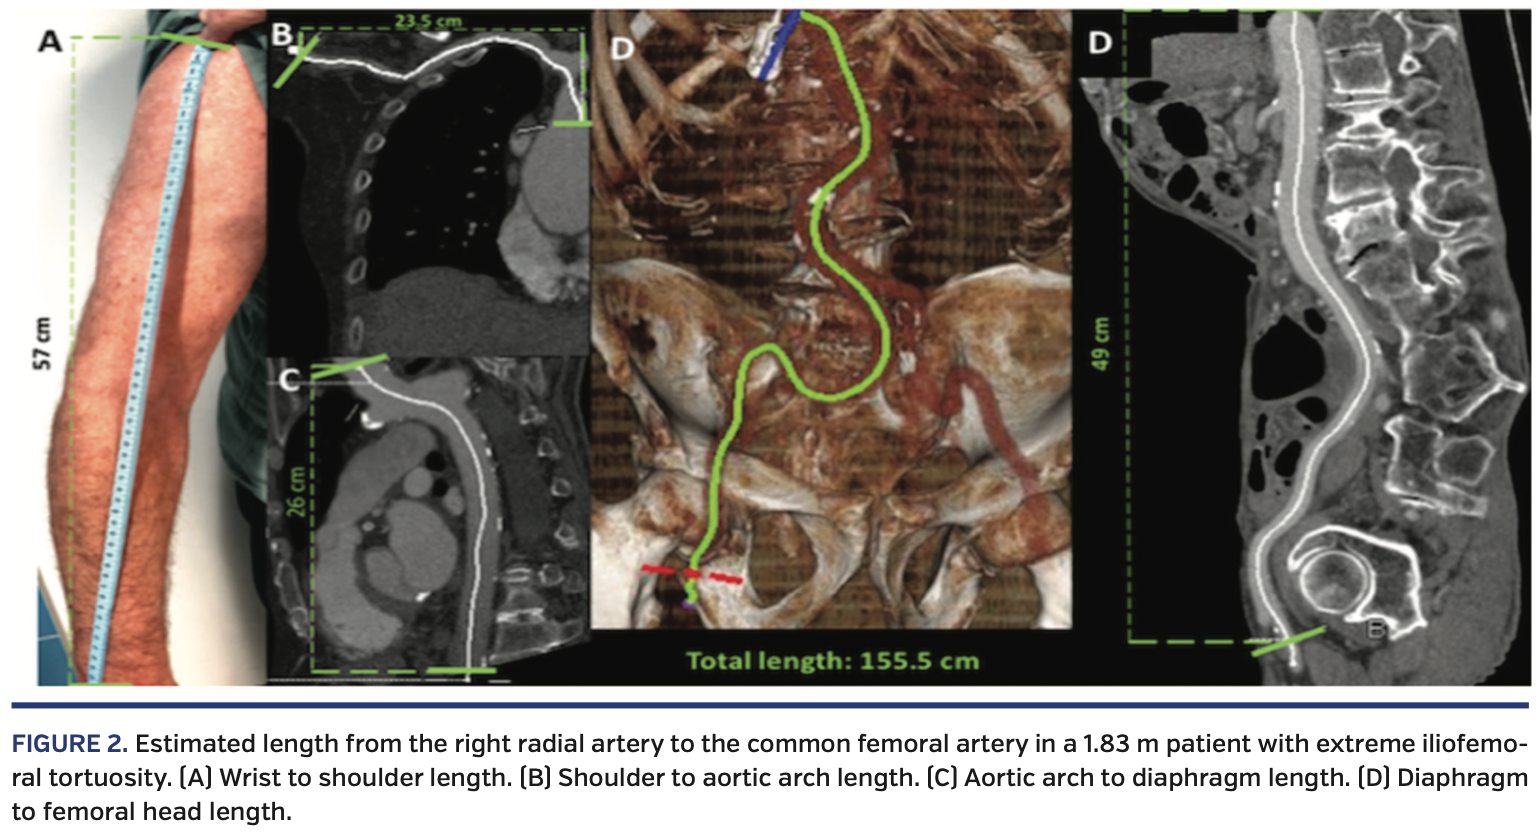

Transradial Crossover Balloon Occlusion Technique for Primary Access Occlusion Valve When the button is pressed gas flow. Multidetector computed tomography (ct) is an important tool for assessing the risk of coronary occlusion in native valve tavr. The purpose of the valve is to restrict the exhaust side of. 8,13 although the optimal methodology for ct screening of the risk of coronary occlusion in the context of viv is still in. Occlusion Valve.

Transradial Crossover Balloon Occlusion Technique for Primary Access Occlusion Valve The purpose of the valve is to restrict the exhaust side of. When the button is pressed gas flow. Multidetector computed tomography (ct) is an important tool for assessing the risk of coronary occlusion in native valve tavr. In as few as 30 seconds, the pressure that builds up. 8,13 although the optimal methodology for ct screening of the risk. Occlusion Valve.